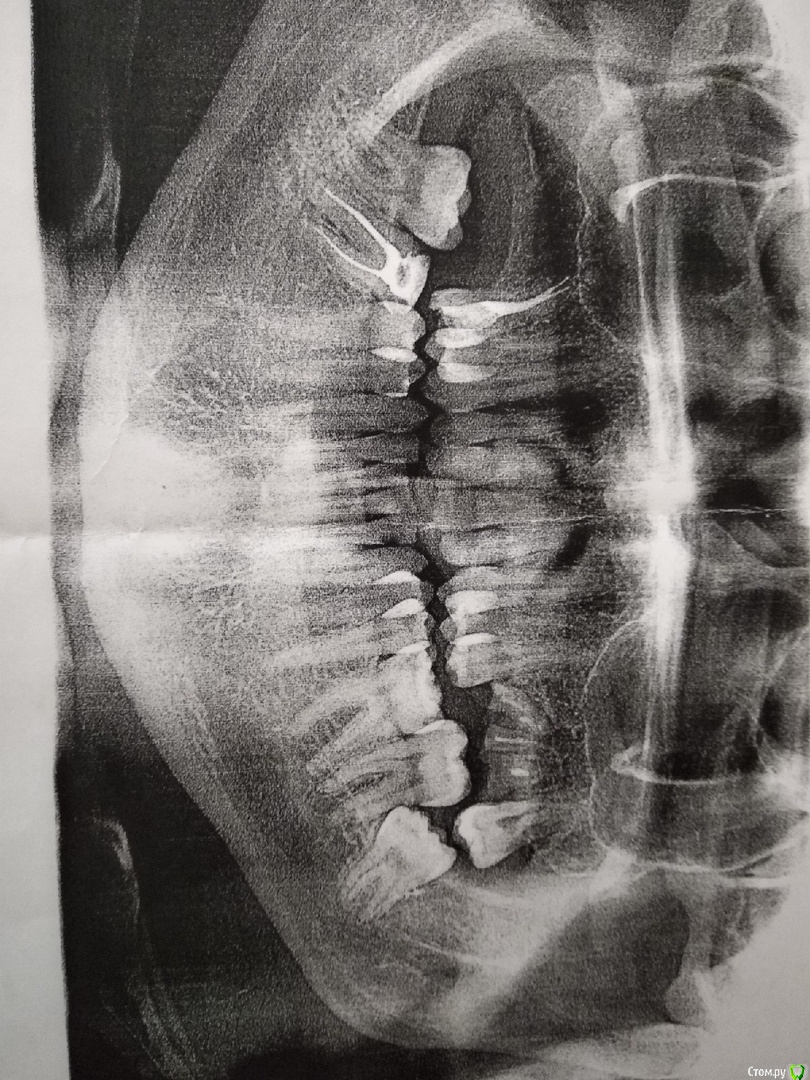

kleio Опубликовано 27 февраля, 2019 Поделиться Опубликовано 27 февраля, 2019 (изменено) Всем привет, у меня такая ситуация. Мне 24 года, несколько лет назад потерял много зубов, а именно: верхняя челюсть справа(18, 17, 16) верхняя челюсть слева (26, 27) - остались только корни. Одного не хватает на нижней челюсти справа (46). Был на консультации у имплантолога и нескольких ортодонтов. Как оказалось нижние зубы которые были под удаленными сверху сильно выдвинулись по вертикали - феномен Попова-Годона. Все ортодонты предлагают поставить брекеты с удалением нижних зубов: справа - 47, слева - 37, т.к. прикус мезиальный. Проблема в том, что удалять зубы мне как то не хочется по нескольким причинам:1) долгое время будет большое пространство из-за удаленных зубов;2) жевательных зубов и так мало, сложно пережевывать пищу; Есть возможность другого подхода лечения? Например вколотить зубы на место с помощью микроимплантов или каких нибудь капп. Изменено 27 февраля, 2019 пользователем kleio Ссылка на комментарий